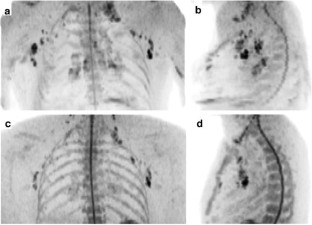

The purpose was to provide a diffusion-weighted whole-body magnetic resonance (MR) imaging sequence with background body signal suppression (DWIBS) at 3.0 Tesla. A diffusion-weighted spin-echo echo-planar imaging sequence was combined with the following methods of fat suppression: short TI inversion recovery (STIR), spectral attenuated inversion recovery (SPAIR), and spectral presaturation by inversion recovery (SPIR). Optimized sequences were implemented on a 3.0- and a 1.5-Tesla system and evaluated in three healthy volunteers and six patients with various lesions in the neck, chest, and abdomen on the basis of reconstructed maximum intensity projection images. In one patient with metastases of malignant melanoma, DWIBS was compared with 18F-fluorodeoxyglucose positron emission tomography (FDG-PET). Good fat suppression for all regions and diagnostic image quality in all cases could be obtained at 3.0 Tesla with the STIR method. In comparison with 1.5 Tesla, DWIBS images at 3.0 Tesla were judged to provide a better lesion-to-bone tissue contrast. However, larger susceptibility-induced image distortions and signal intensity losses, stronger blurring artifacts, and more pronounced motion artifacts degraded the image quality at 3.0 Tesla. A good correlation was found between the metastases as depicted by DWIBS and those as visualized by FDG-PET. DWIBS is feasible at 3.0 Tesla with diagnostic image quality.

Fig. 2